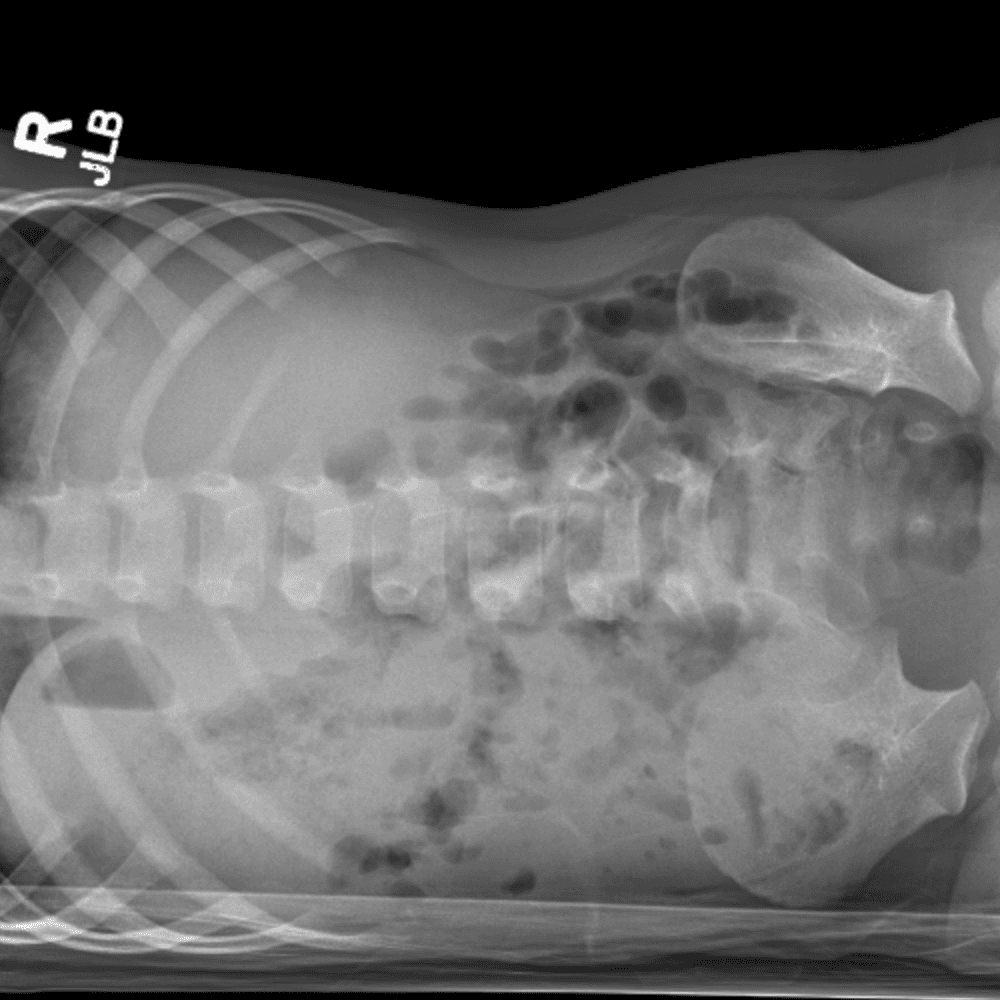

Peds Abdomen

Practice

Simulates call by including subtle or difficult cases and some normals.

30 cases